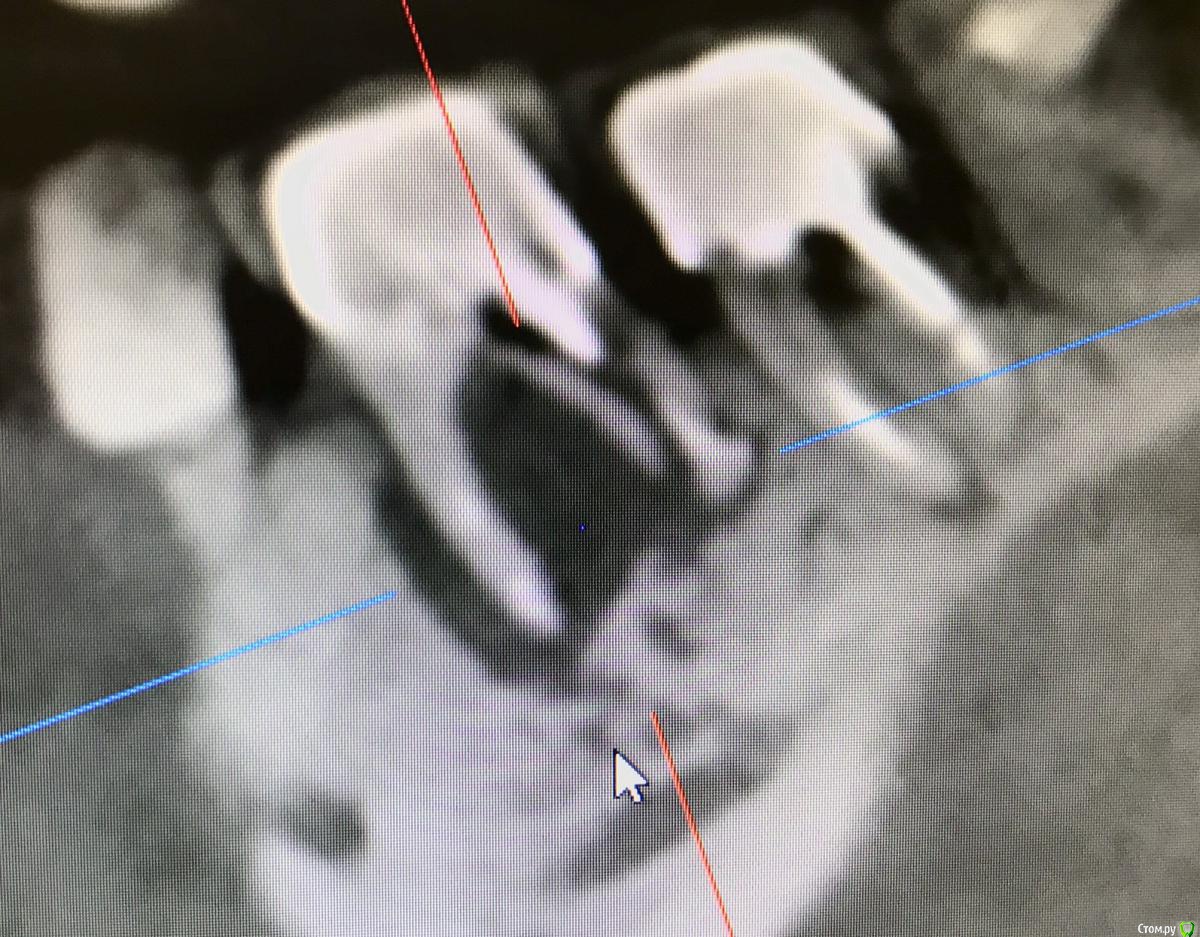

колесников Опубликовано 22 апреля, 2019 Поделиться Опубликовано 22 апреля, 2019 (изменено) И снова профайл спасает жизнь (облегчает жизнь имплантолога)Стандартная ситуация:36 периодонтит в стадии обострения с грануляциями,эксудацией,резорбцией компактной пластинки,дефицитом прикреплённой слизистой вестибулярного. Одна хирургия. Ноябрь 2018. Удаление,кюретаж,имплант Astra tech profile 4.5x9 под заглушку,торк около нуля. Вестибулярного сст,консервация графтом Sureoss 0,5 чипс с APRF,закрытие шайбой по Ноймайеру. Через неделю шайба несостоятельна-удалена. Пациентка созрела на удаление 37го. Выполнена декоронация в связи с отъездом пациентки,далее через 2 недели удаление и имплантация 37го. Промежуточный осмотр в январе. В марте установлены формирователи . Апрель контрольный осмотр. Периотест -5. Направлена на протезирование. Изменено 22 апреля, 2019 пользователем колесников 4 Ссылка на комментарий